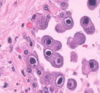

The histological sample below is indicavtive of what infection?

CMV

The histological slide shows Owl’s eye inclusions, which are indicative of CMV-infected cells.

CMV has what characteristic histological appearence?

Owl’s eyes nuclear inclusions

Remember: you “C” with your eyes, so CMV is indicated by owl’s eyes

Owl’s eyes are inclusion bodies surrounded by a halo in CMV infected cells.